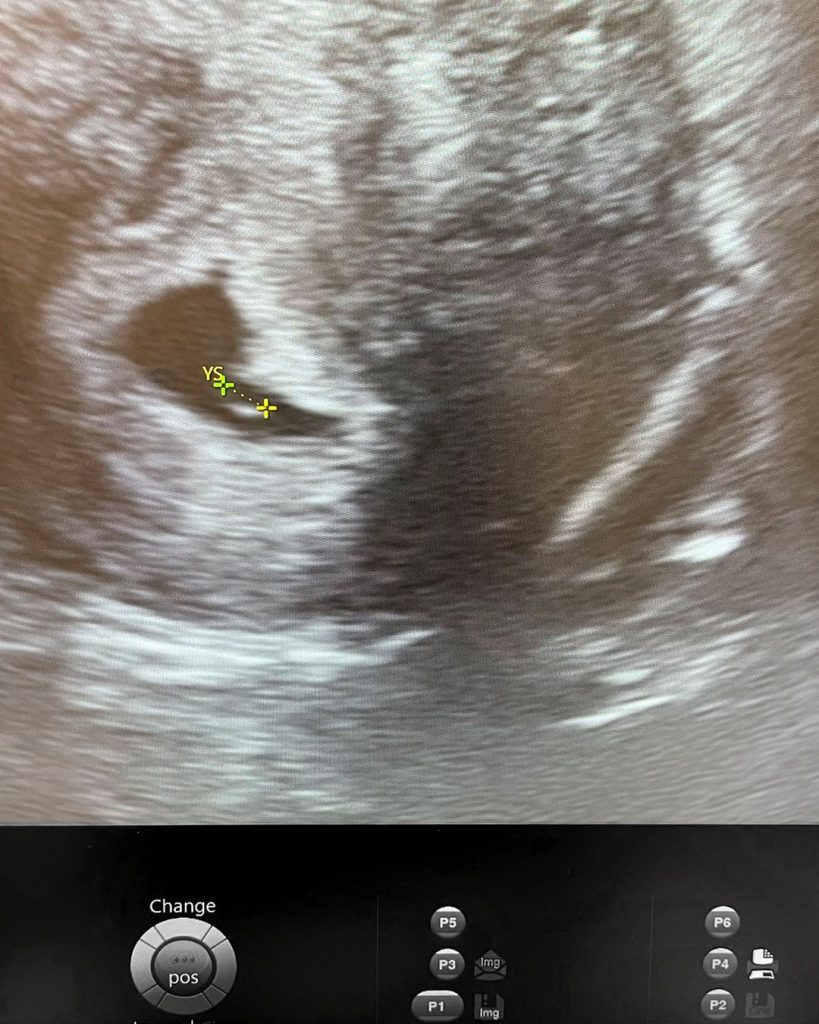

Încep să-i explic cu blândețe opțiunile pe care le are: crioprezervarea de ovocite, crioprezervarea de embrioni și crioprezervarea de țesut ovarian. Cum nu are un partener, crioprezervarea de embrioni nu o ajuta, pentru că nu vrea să folosească la întâmplare sperma unui donator. Deși în alte părți ale lumii crioprezervarea de țesut ovarian a intrat deja în practica curentă, la noi în țară nu se practică. Așa că singura opțiune pe care i-o pot oferi este crioprezervarea de ovocite. Mă întreabă dacă o putem face în cateva zile. Îi explic că pentru a recolta cât mai multe ovocite mature, îi voi da medicație hormonală, similar tratamentului pentru o procedură de fertilizare in vitro. Perioada în care își va administra medicația injectabilă este de 8-12 zile, timp în care va veni la clinică de câteva ori, pentru ecografii și analize de sânge. Când foliculii vor ajunge la o dimensiune bună, atunci vom putea să facem injecția finală, ce ajută maturarea ovocitelor. De-abia apoi vom face puncția ovariană, când voi scoate din foliculii ovocitele. Îi explic în ce constă procedura, că se face sub anestezie generală și că nu va simți nimic.

Am luat legătura cu oncologul ei, a început tratamentul peste 2 zile, după 13 zile de tratament am făcut puncția ovariană și are acum 11 ovocite congelate.